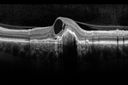

62 year old women with poor vision in the left eye for 20 years and 2 months of vision loss in the right and better eye. VA 20/80 right eye, 20/800 left eye. Right eye has a CNVM with subretinal blood and fluid. The left eye has a macular scar